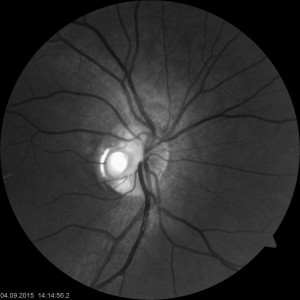

Grubenpapille (siehe Anmerkung)

Papillengrube (аббревиатура: Grube)